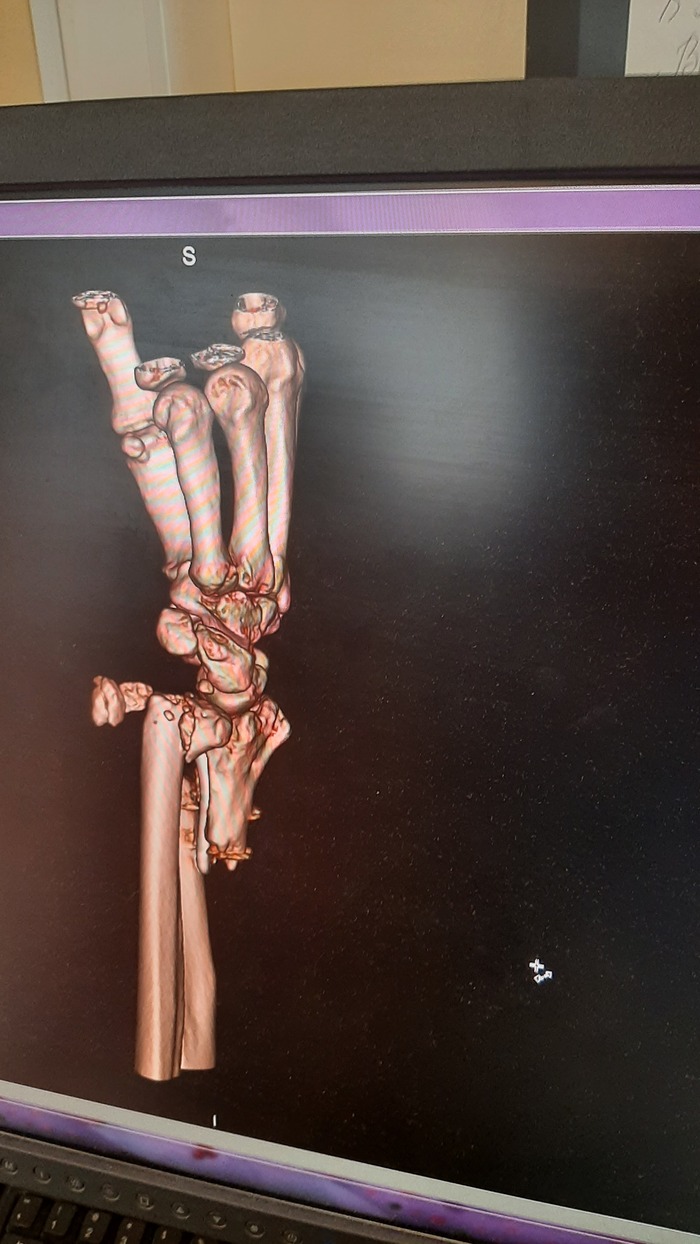

Ну и очень много рентгеновских снимков